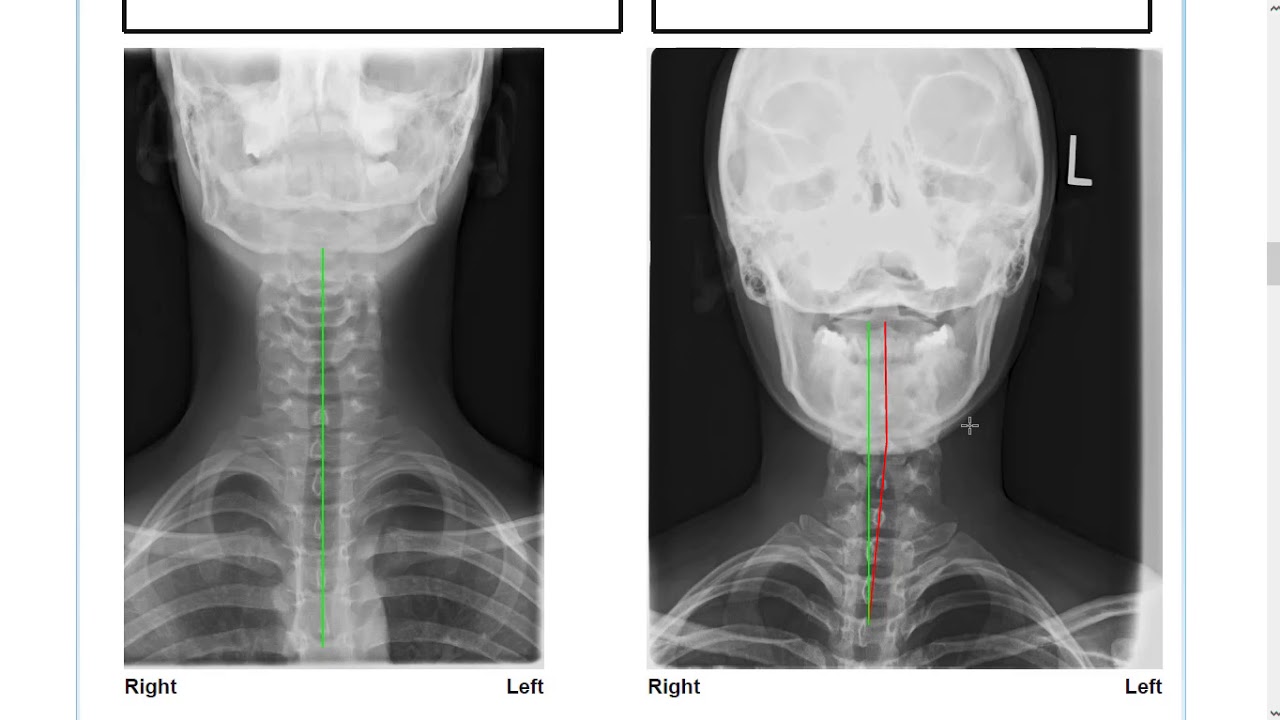

Do you ever feel like your spine is out of alignment and causing you to have back pain, neck pain or headaches? As chiropractors in Newark, our job is to ensure that your spine is positioned and functioning as well as possible, but how do we figure out whether or not your spine is in alignment? And if it's out of alignment, what direction has it shifted, and how far out of position is it?

Join Dr. Travis McKay as he leads you through a sample x-ray report. He'll discuss how we evaluate our patient's spine to easily show them where their spine is versus where it should be, and what it will take to get it back to normal. He'll also talk about why that normal alignment is so important and why it needs to be improved in order for our patients to feel and function better!